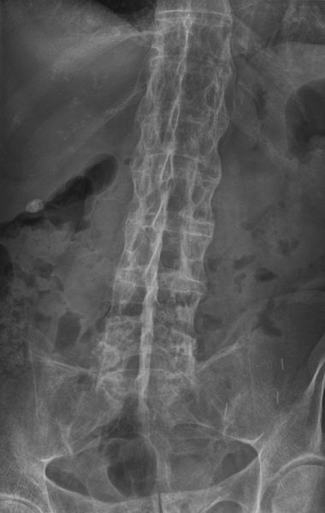

- Spinal X-Ray:

- Squaring of vertebral bodies

- Syndesmophytes → “bamboo spine”